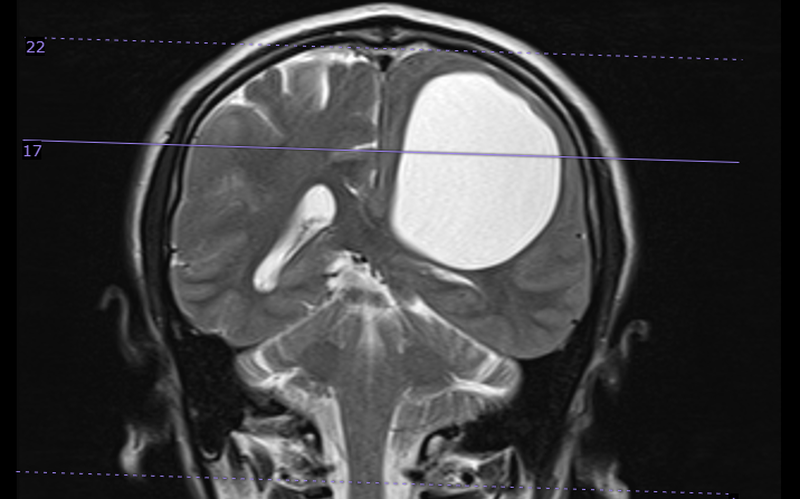

Sau khi tiến hành thăm khám, chụp chiếu, kết hợp với các biểu hiện lâm sàng, người bệnh được hội chẩn và chẩn đoán đa u nang trong não, chưa loại trừ nang sán não. Trong nhu mô não có rất nhiều nang to, nhỏ. Trong đó, nang kén lớn nhất kích thước khoảng 5 x 7cm, đè ép nhu mô não khiến người bệnh yếu, liệt nửa người.

Người bệnh được chỉ định phẫu thuật lấy u (nang sán), giải phóng nang chèn ép não, gửi mô bệnh học và làm giải phẫu bệnh.

Ca phẫu thuật diễn ra thuận lợi, bệnh phẩm được gửi Khoa Giải phẫu bệnh cho kết quả đúng như hội chẩn: Đa nang kén sán não.